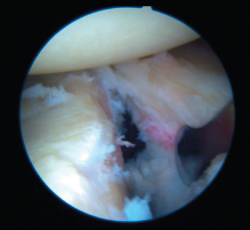

In the case of an impingement or off-track lesion, the risk of relapse increases considerably(33); in these cases the required surgical manoeuvre should convert the HSL into an on-track lesion again or into a non-impingement lesion. The remplissage technique has been successfully used for this purpose(64) and involves fixation of the posterior capsule and part of the infraspinatus tendon (capsulotenodesis) to the bone defect of the humeral head. Connolly et al.(65) proposed this technique as an open procedure four decades ago, though it was Wolf in 2004 who first described the arthroscopic technique as a modification of the open procedure. Many authors have reported good outcomes combining arthroscopic Bankart repair with remplissage. Wolf et al.(66) reported their findings after up to 10 years of follow-up, with the recording of recurrence in only two out of 45 patients (4.4%). Boileau et al.(61) used this procedure in 47 of 459 shoulders, and only one shoulder (2.1%) suffered recurrent instability. Recent systematic reviews have found the overall recurrence rate after combining both techniques to range from 3.4% to 5.4%, without important joint balance restrictions(67,68). As an undesired effect, the technique may produce a certain decrease in mobility, especially referred to external rotation, though it considerably lessens the instability recurrence rate(61).